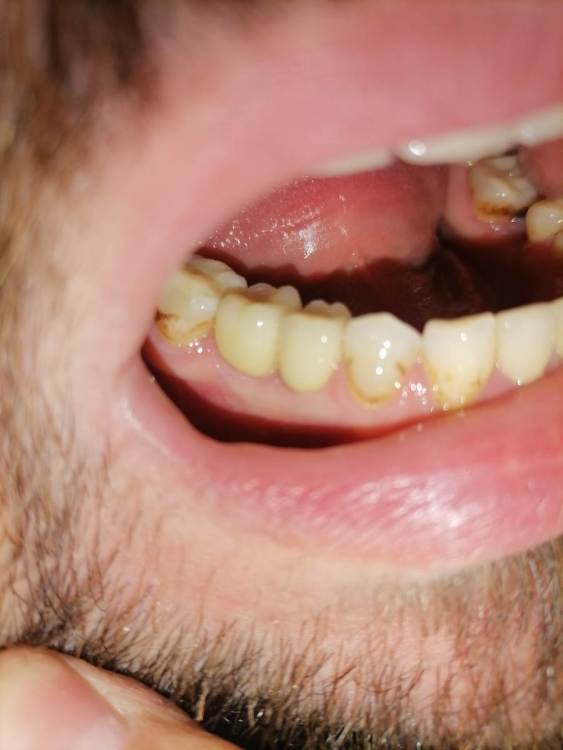

Добрый день уважаемые доктора. После установки коронок на импланты, беспокоит что на контрольном снимке оголилось 2 витка резьбы импланта.

Сами импланты установлены в ноябре.  Коронки на них поставили месяц  назад, закрутили с усилием 25 ньютонов, и поставили временную пломбу . Отправили на месяц гулять. Сегодня сделал снимок, пришёл к врачу врач сказала что все отлично. Докрутила на 35 и поставила постоянную пломбу. Но меня беспокоит что ушло несколько витков резьбы, хотелось бы услышать ваше мнение, скажите это нормально? По ощущениям ничего не беспокоит, жую без проблем.